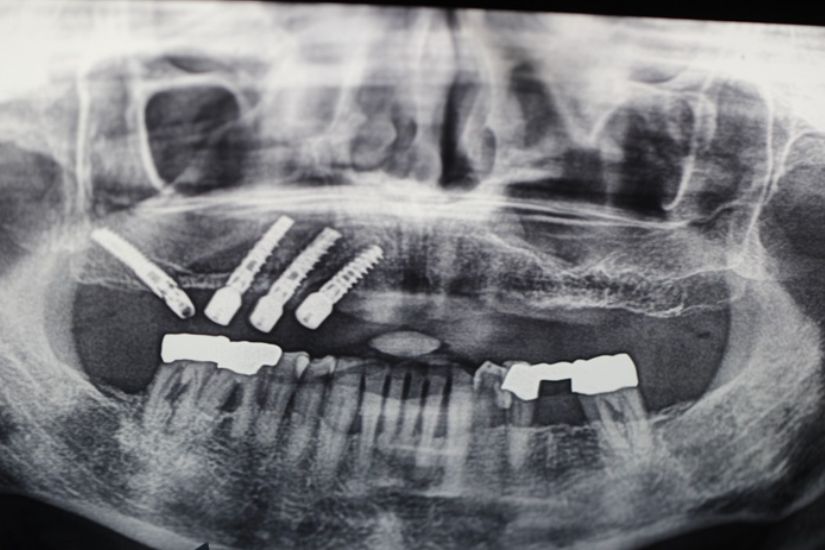

Dental Rehabilitation Using Alpha Dent Implant in Case of Reconstructed Mandible after Excision of Ossifying Fibroma

Dental Rehabilitation Using Alpha Dent Implant in Case of Reconstructed Mandible after Excision of Ossifying Fibroma Dr. Parit Ladani MDS